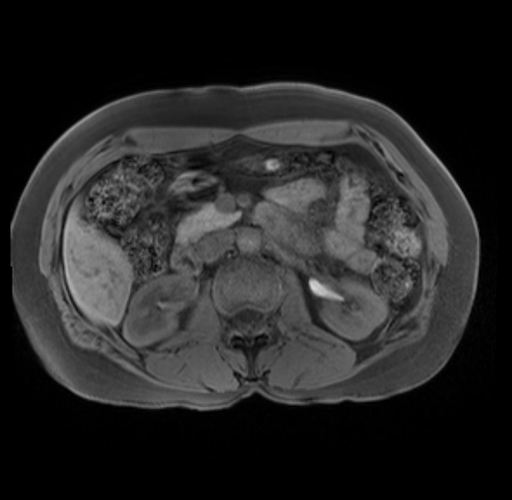

Imaging Analysis

Look through the patient's CT scan to identify any areas of concern for the necessary procedure.

Based on your CT findings, which issue(s) are present and would give reason for "planned slowing down moment(s)" in this case?